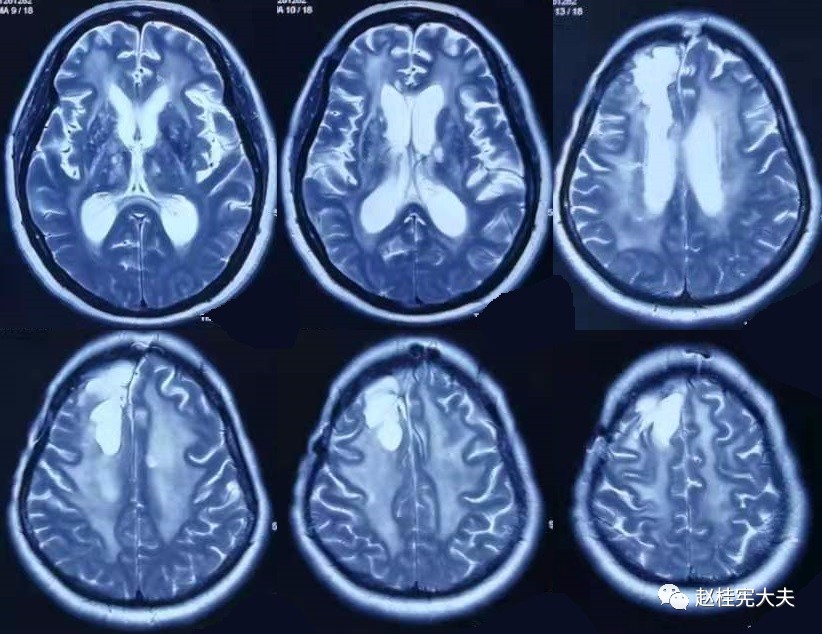

为了更直观,我们先看看其中1例患者的脑白质病变影像学的改变吧:

2017.10

可以看到,随着时间的延长,脑白质的T2异常信号范围不断扩大,并且出现了脑室扩大,脑萎缩。